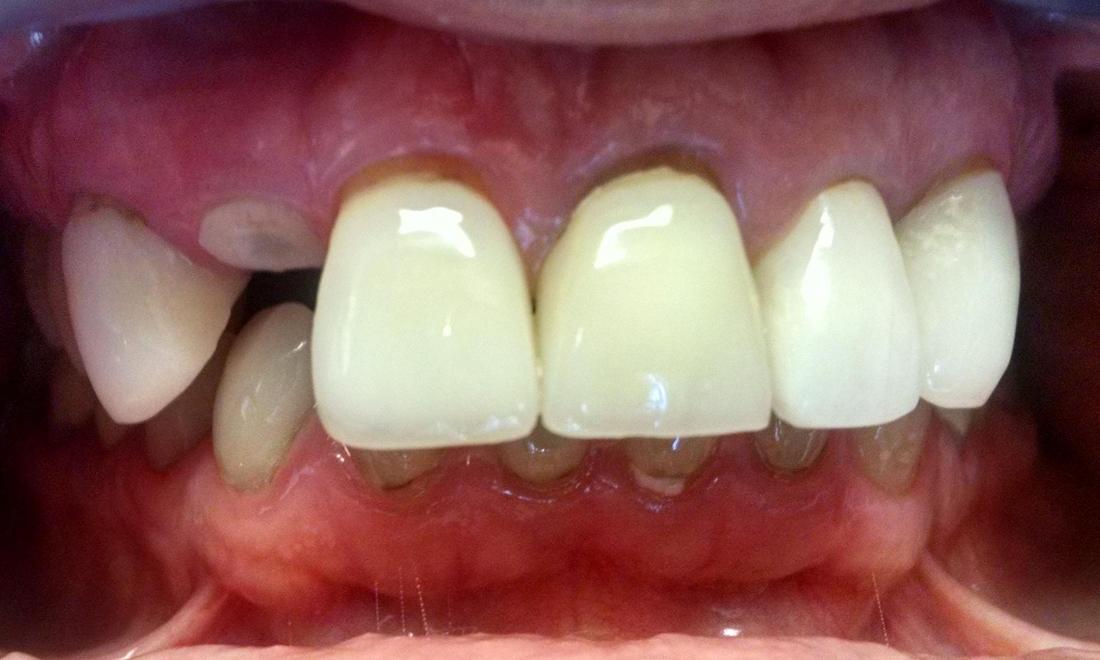

This young lady developed decay and a loose post under a crown. Unfortunately, the tooth could not be repaired and was removed. After a period of healing, a dental implant was placed by Dr. Brad Jordan. The final porcelain crown matches the crowns on her other front teeth very well.